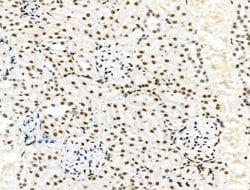

Invitrogen™ Phospho-PDX1 (Ser66) Polyclonal Antibody

Antibody detects endogenous levels of PDX1 only when phosphorylated at Ser66.

| Immunohistochemistry (Paraffin), Western Blot, Immunocytochemistry | |

| A synthesized peptide derived from human PDX1(Accession P52945), corresponding to amino acid residues around phosphorylated Ser66. | |